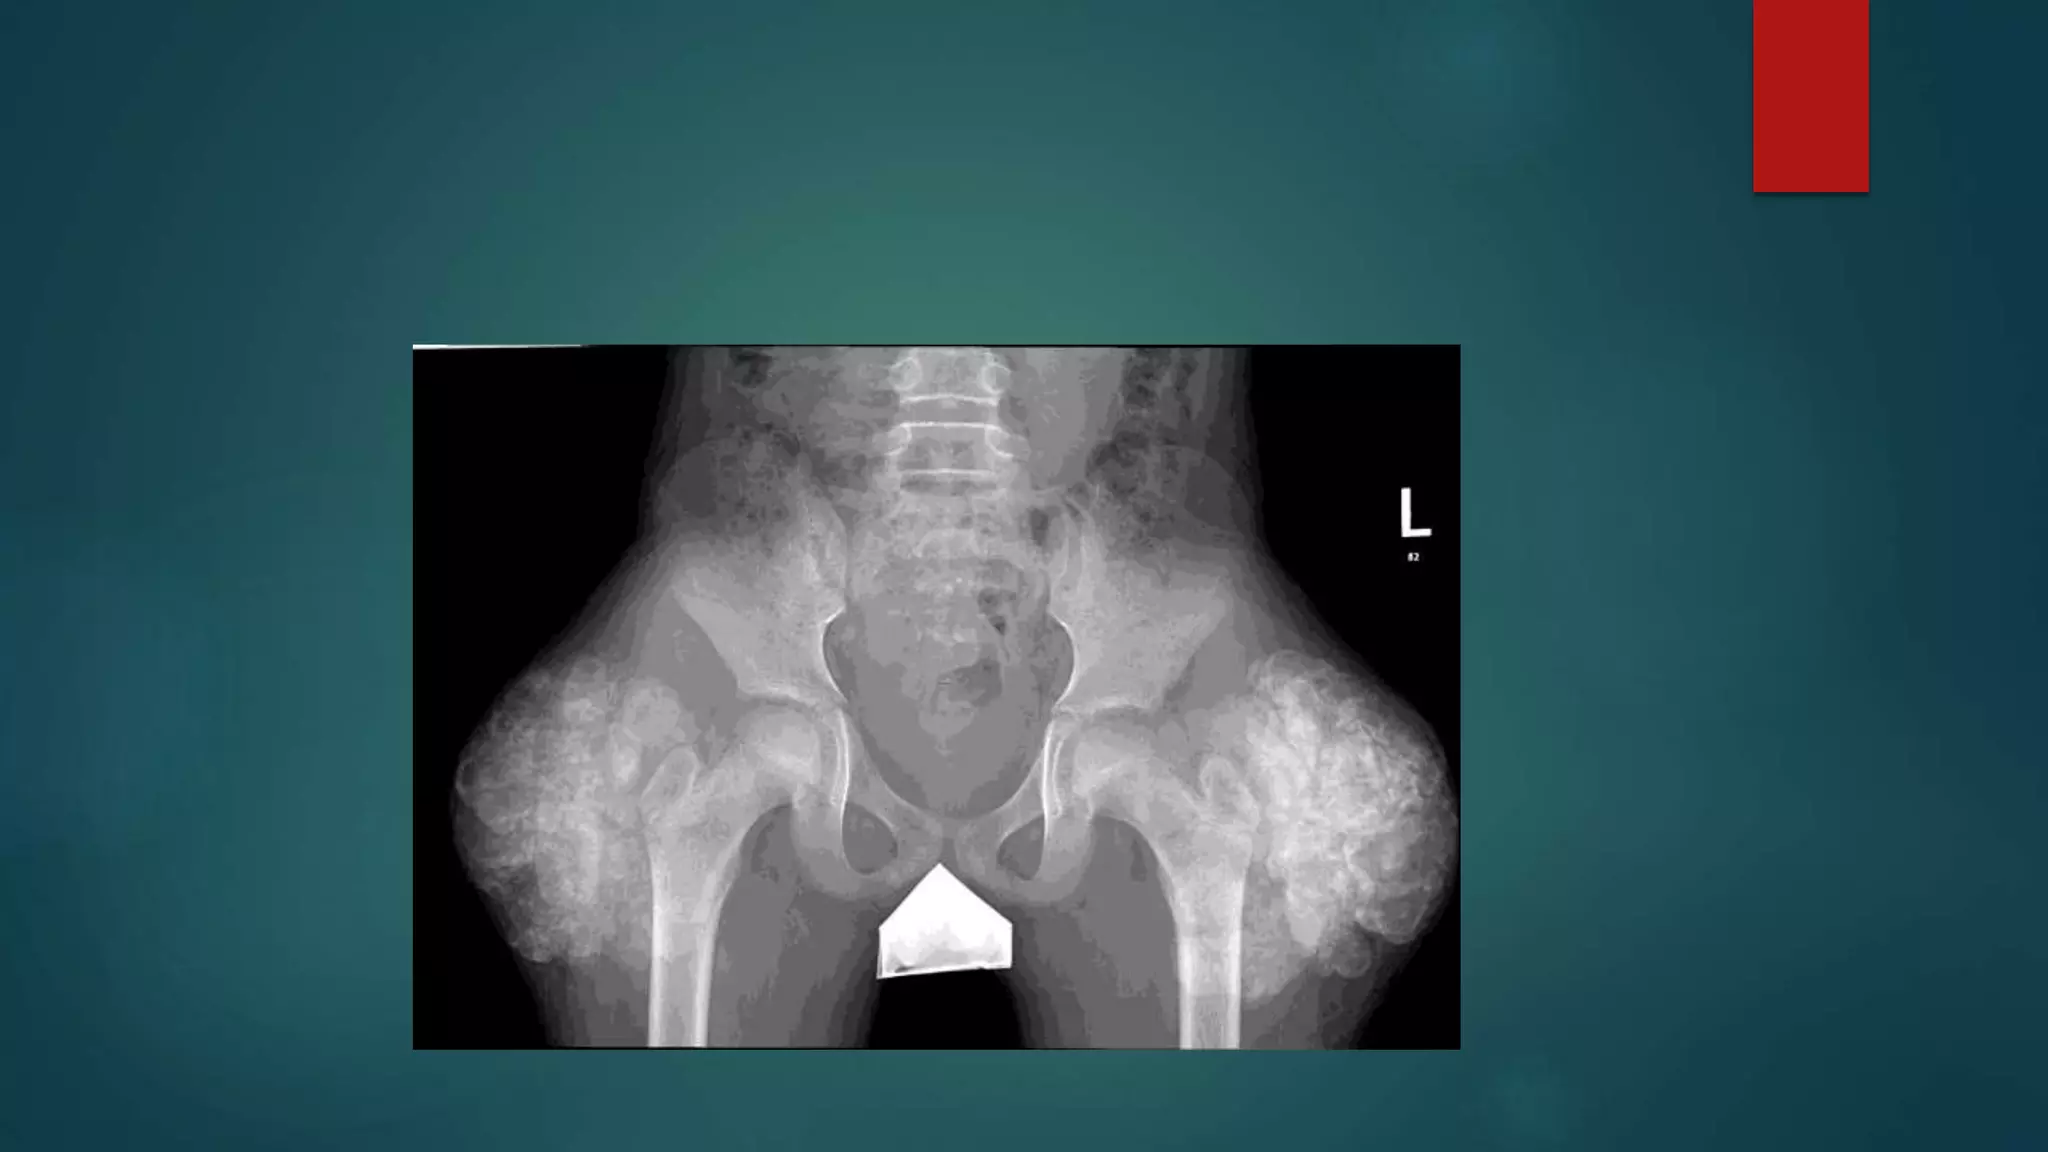

PAGETS

Signs of Paget’s disease

There are many Paget disease-related signs,

listed here and described in the modality-

specific sections below:

•banana fracture

•blade of grass sign

•cotton wool appearance of bone

•ivory vertebra sign

•jigsaw pattern bone or mosaic pattern bone

•Lincoln sign

•Looser zones

•Mickey Mouse sign

•osteoporosis circumscripta

•picture frame vertebra

•Tam o' Shanter sign

Fibrous Dysplasia